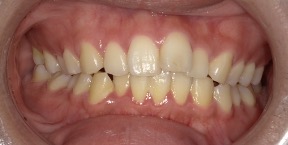

30歳女性のビフォーアフター

| 診断 | 叢生 |

| 治療方針 | 治療方針:インビザラインシステムにて主にIPR(歯と歯の間をわずかに削合してスペースを獲得する方法)を組み込んだ動的矯正治療を行い、叢生を改善後、保定を行う。 |

| 治療費 ※ | 96万5千円(診断、型取り、矯正中のメンテナンス、保定装置を含む料金) |

| 治療期間 | 1年8か月 |

| リスク | 1日20時間以上マウスピースを使用できない場合、歯が動かなかったり、想定しない誤差により不完全に終わる可能性がある。装着時や食事時に痛みを伴う。歯肉退縮や虫歯になるおそれがある。また、指導通りに装着できていない場合や適切なブラッシングが出来ていないとそのリスクが高くなる。歯根が短くなることがある。ごくまれに歯の神経が損傷してしまうことがある。過去にぶつけたり深い虫歯治療をしたことがあるとそのリスクはやや高くなる。矯正後には保定装置が必要。適切な使用ができない場合、後戻りの原因となる。将来的に歯並びが動いて再矯正が必要な場合がある。舌癖(舌で歯を押し出す癖)親知らずが正常に生えていない場合、その可能性がやや高くなる。 |